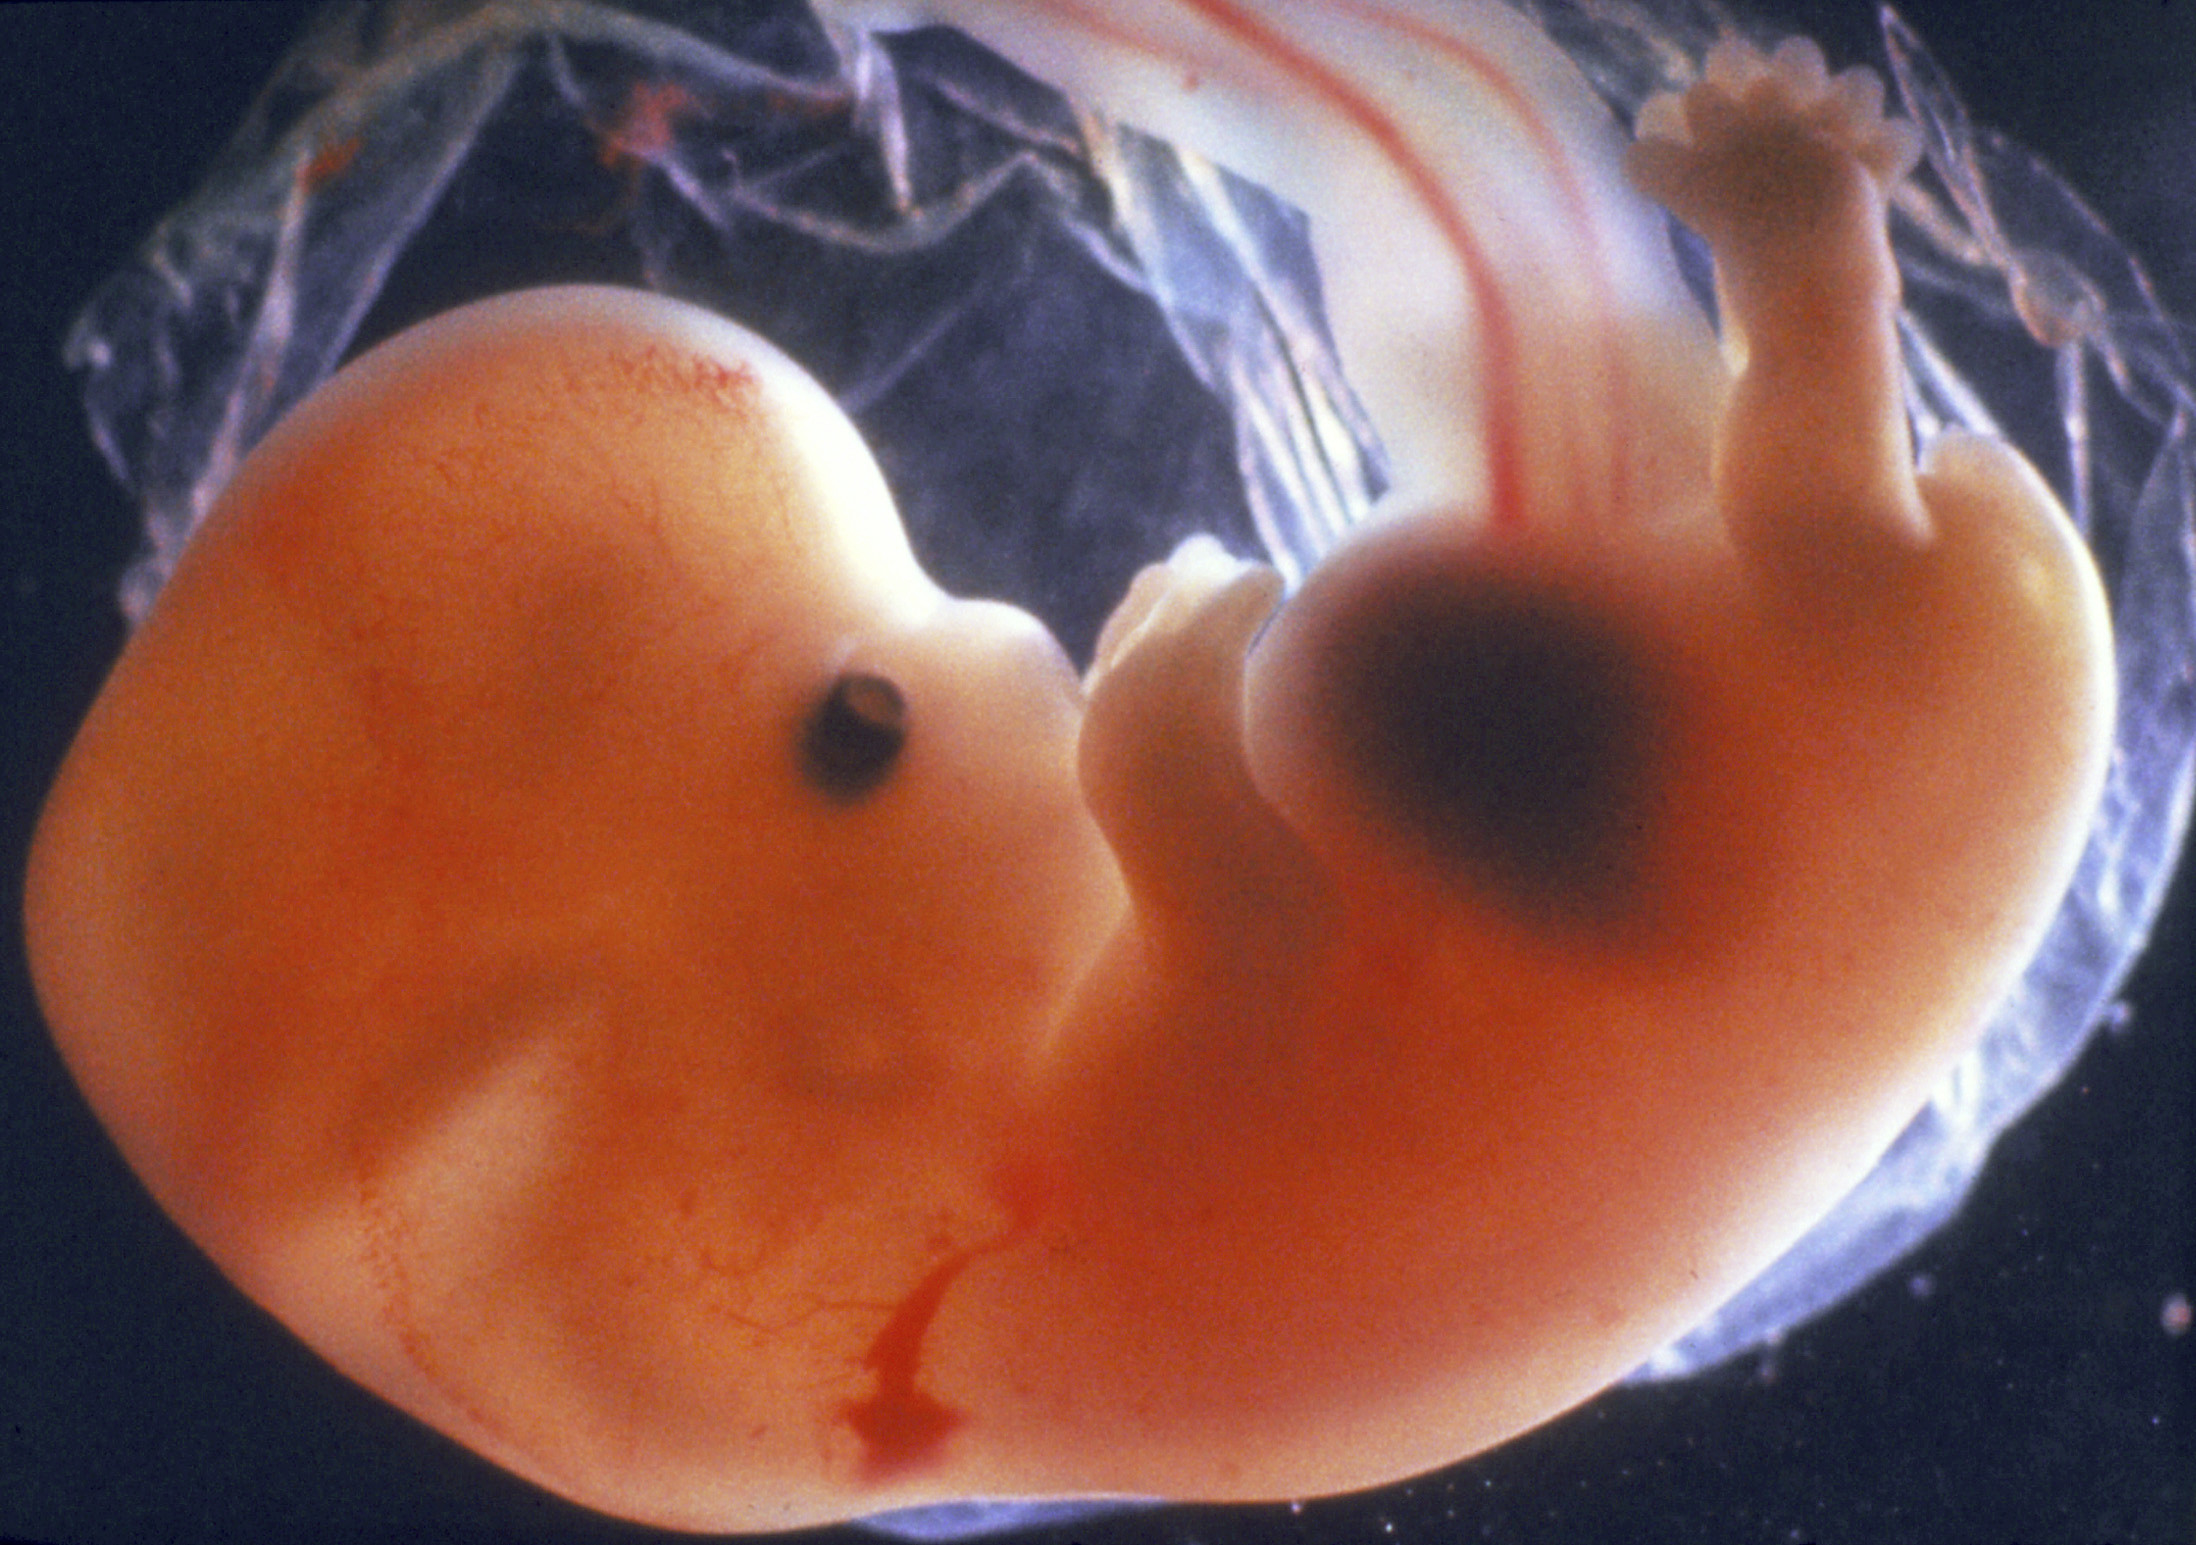

Снимки Леннарта Нильсона: развитие ребенка в утробе

Раздел: Мудрость в фокусе